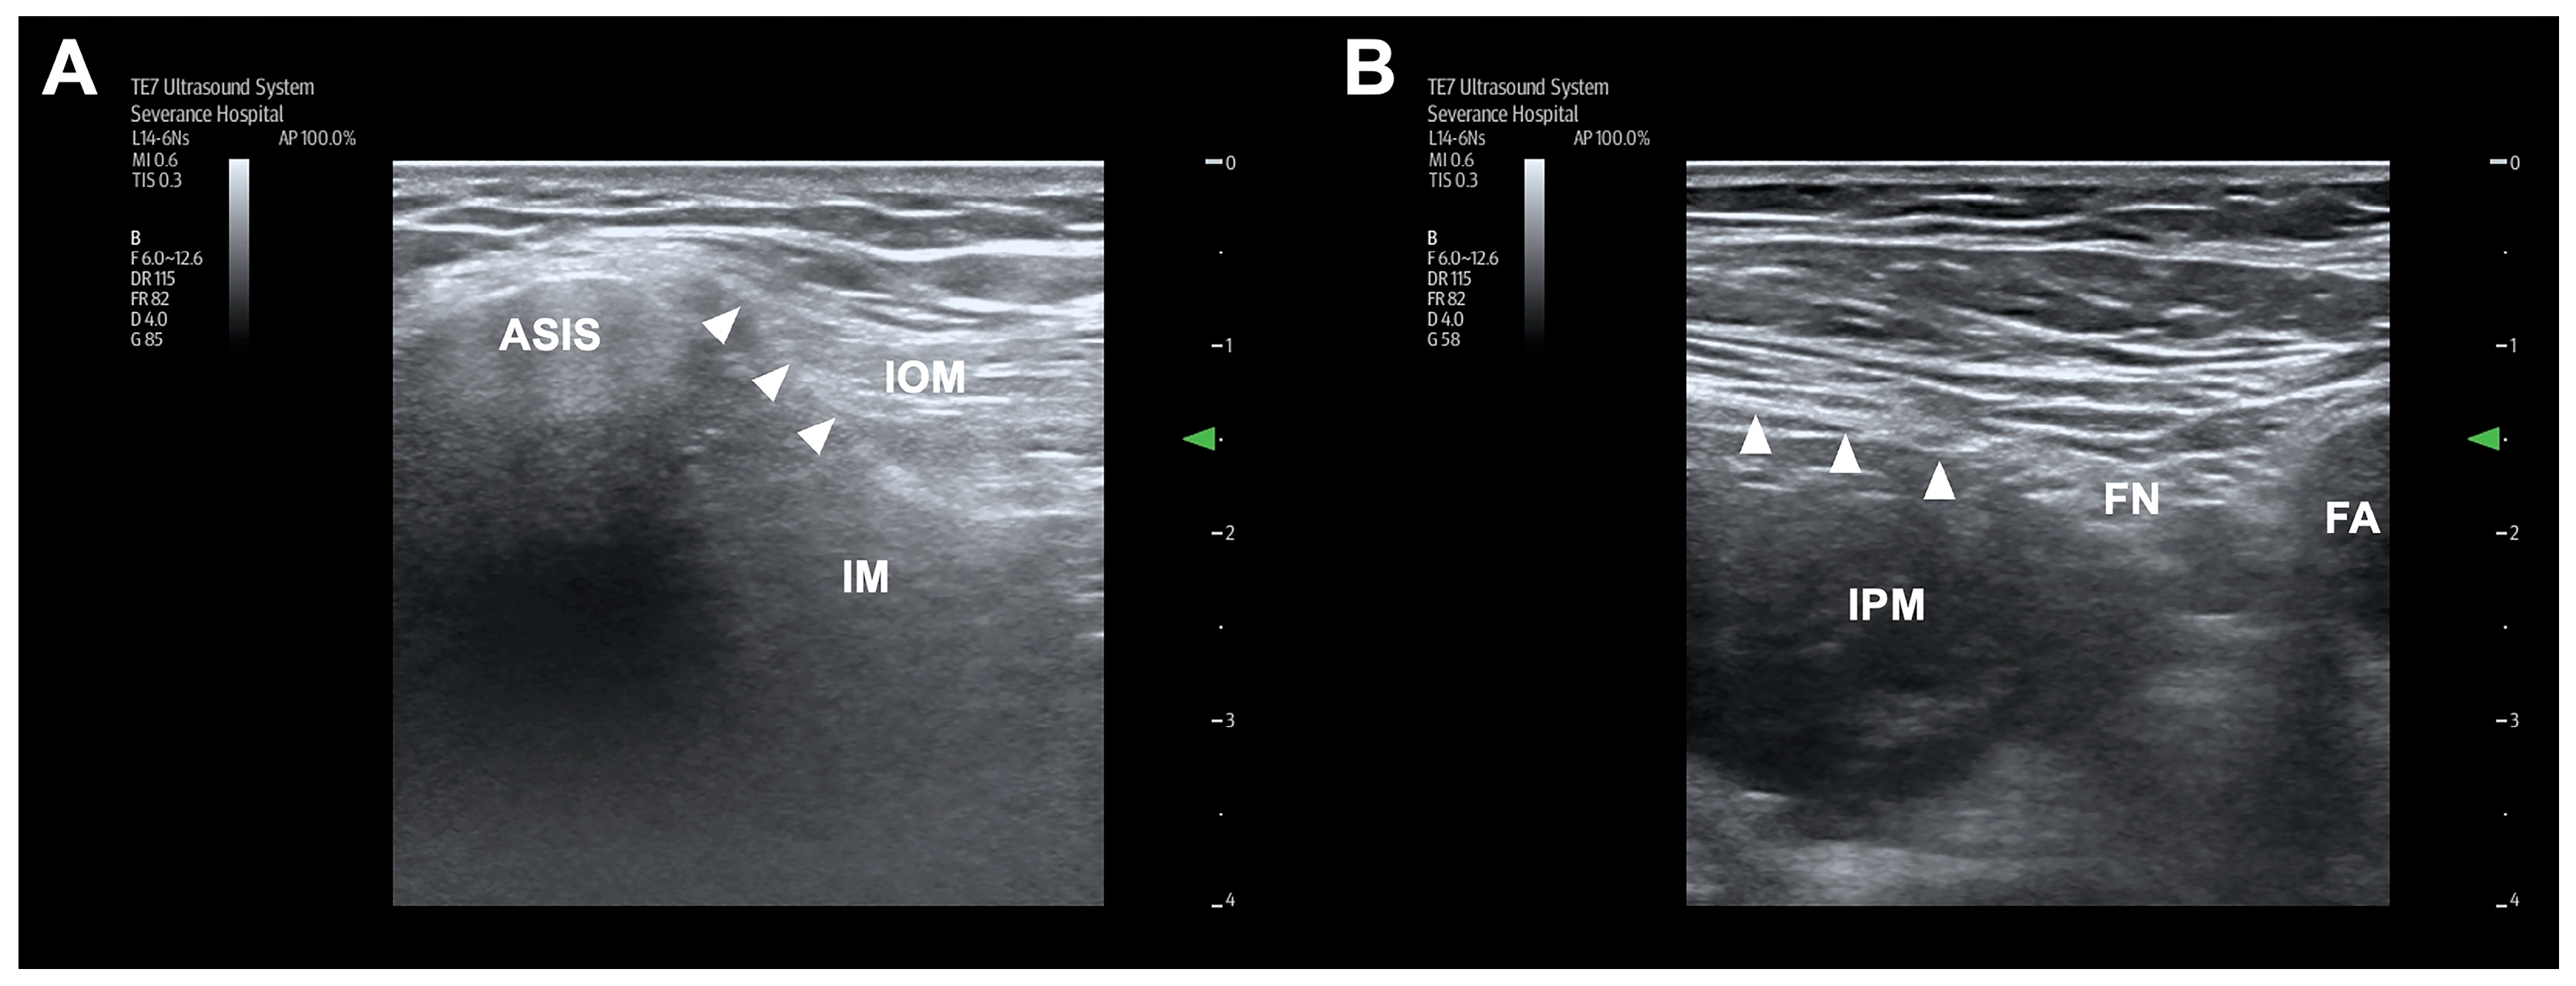

2.1. S-FICB Procedure

2.2. I-FICB Procedure